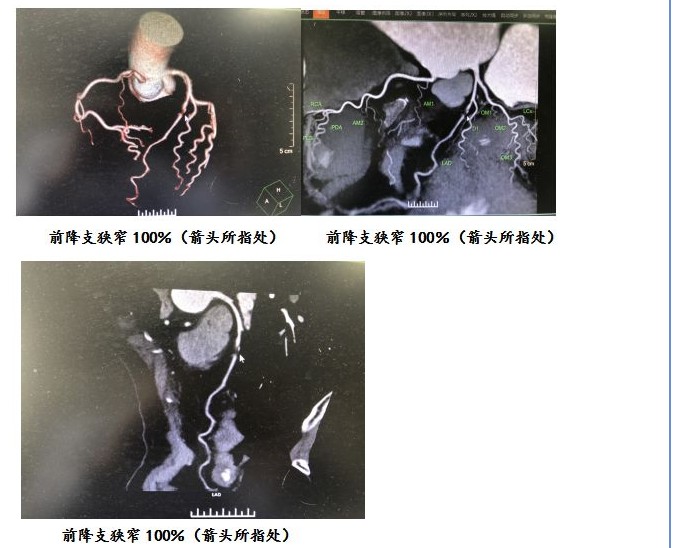

入院后查体无阳性体征,行血常规及生化检查、心脏及腹部彩超、胸部CT等相关检查均无明显异常,24小时动态心电图提示“持续性ST段下移”。结合患者症状发作特点及心电图表现,考虑“冠状动脉粥样硬化性心脏病、不稳定性心绞痛”可能性较大,建议患者进一步行冠脉CTA检查,结果提示“LAD中段可见局限性混合性斑块,局限管腔闭塞(100%),远端血流充盈变淡;LCX近段可见局限性混合性斑块,管腔轻微狭窄”。

冠脉CTA检查结果更加证实了当前诊断,随后在上级医院行冠脉支架植入术,于LAD植入冠脉支架1枚,术后长期服药,定期复查,目前临床症状已基本消失。